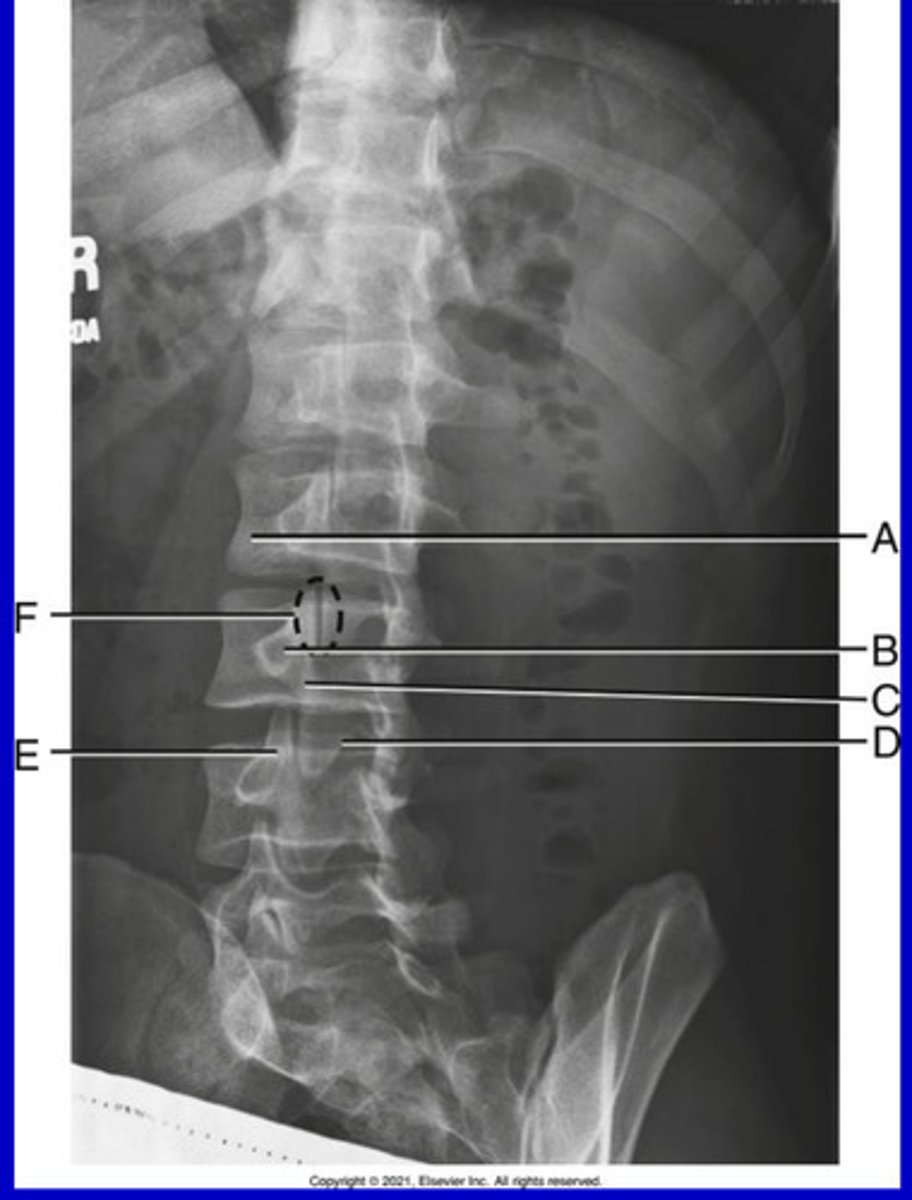

L5 R transverse process

A.

L4 Lower lateral portion

B.

L4 spinous process

C.

L3 R inferior articular process

D.

L4 L superior articular process

E.

L1-2 intervertebral disk space

F.

AP Lumbar

What position?